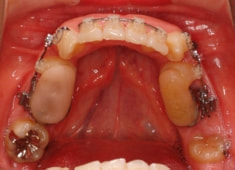

治療開始から1年8ヶ月後